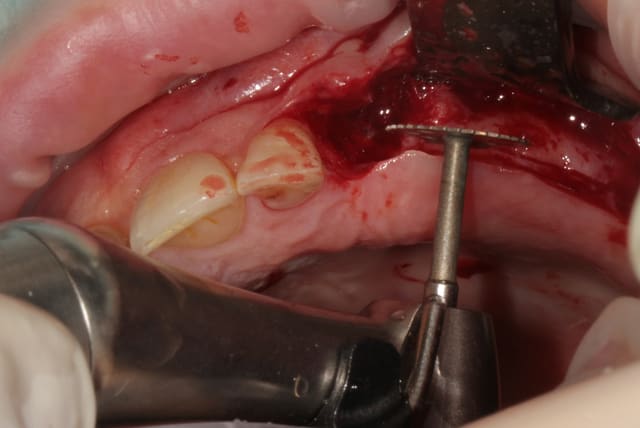

L'intervention se déroulant en 1 temps chirurgical et n'étant qu'un amateur, j'ai choisi des réglages simples en macro automatique afin de suivre le déroulé sans prise de tête.

Guide chirurgical dentaire 02 ekubld - Eugenol

Photo clinique de Posit...

très moyen, aucune profondeur, déformation de l'image(objectif grand angle non adapté au macro dentaire...), couleur non réaliste

Guide +1, photo -1

Celle- là, j'aime bien car on ressent le geste du chirurgien.